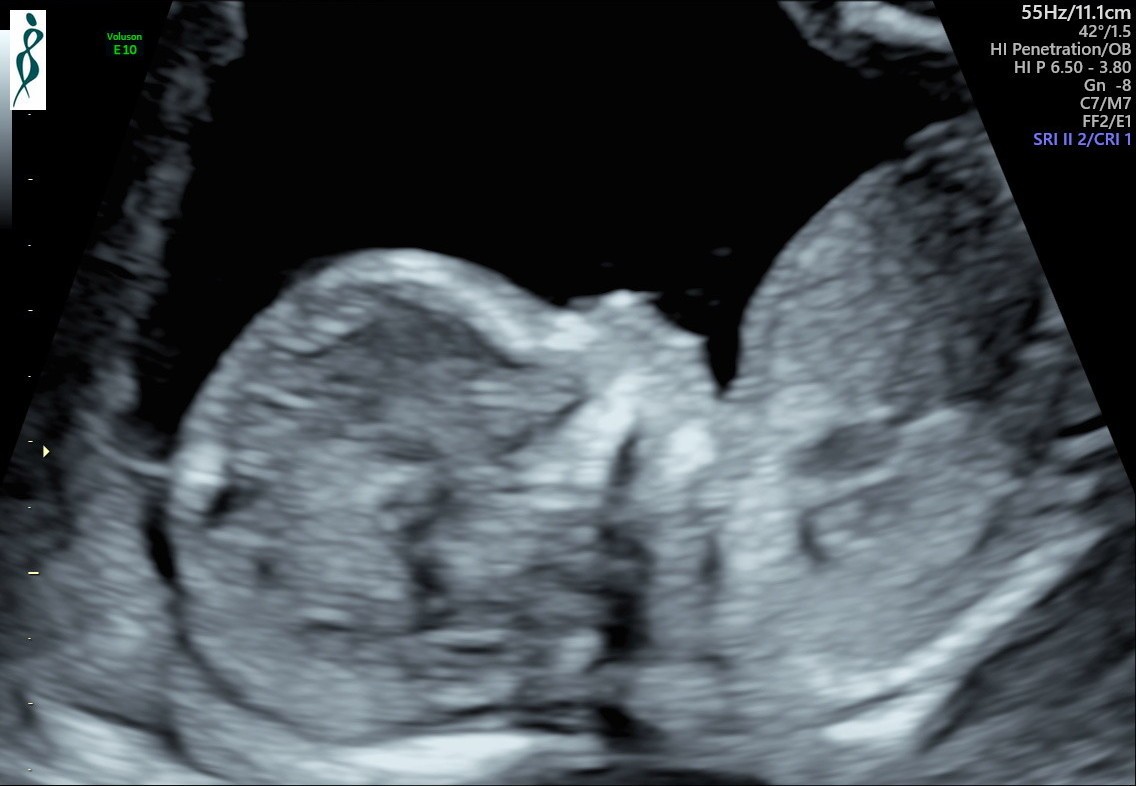

Hej Kobietki 🤗 Pchełka ma się doskonale 😁 Spała na początku badania i zasłaniała sobie buzię łapką, potem się troszkę rozruszała 💗 Jest taaaaaka śliczna 😭😍😭😍😭😍😭😍😭 Mój się przyznał, że też się strasznie denerwował przed tym USG. Teraz przez chwilę będziemy spokojni 😉 EF132B00-F0CA-46D0-918F-C9C1E6B94FED.jpeg6572E766-5AC9-4475-910D-935FEB244FE2.jpeg77D837DD-3B73-4015-919E-F6789011F490.jpeg